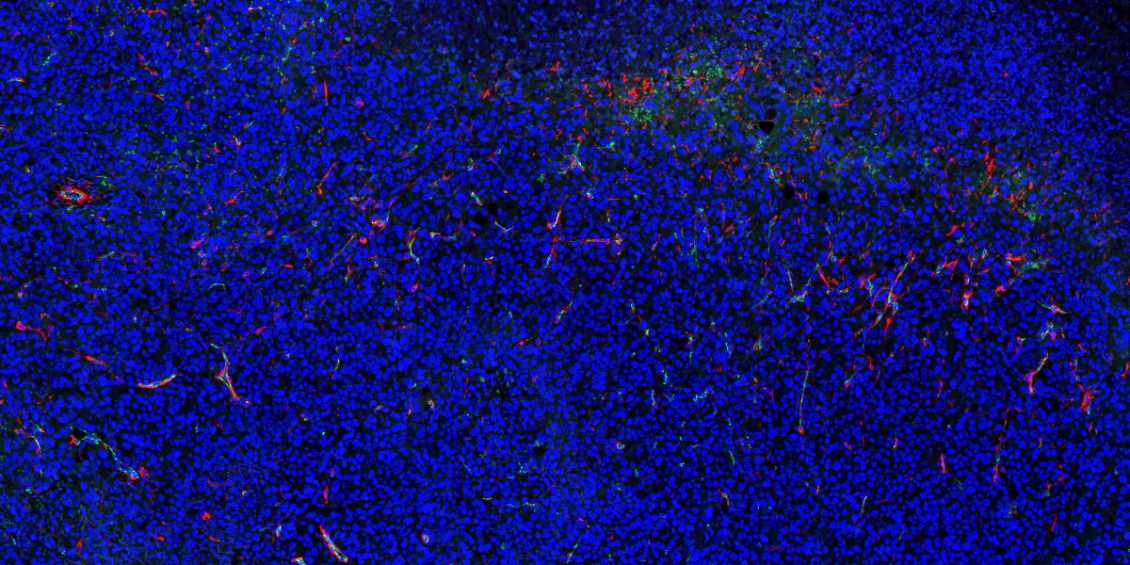

重庆石蜡切片免疫荧光不可避免会产生自发荧光。

1.取材的时候灌注取材,把红细胞冲洗干净;

2.脱蜡必须彻底,封闭、洗涤等过程也需充分;

3.抗体在使用前最好先离心处理并尽量从上方吸取,抗体的浓度过高也会产生自发荧光,所以可以预实验摸清最合适的抗体浓度再进行正式实验;

4.如若自发荧光很强,严重影响染色效果,亦可采用自发荧光去除剂进行去除。